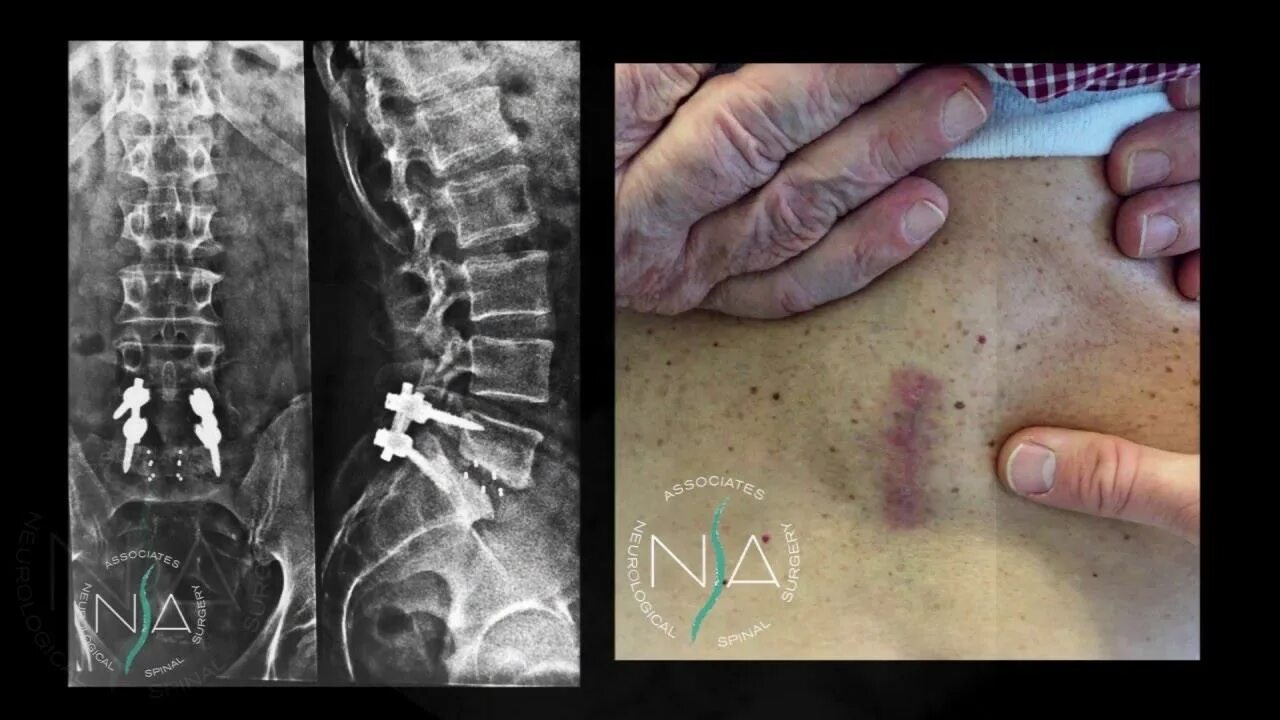

L 5 ni